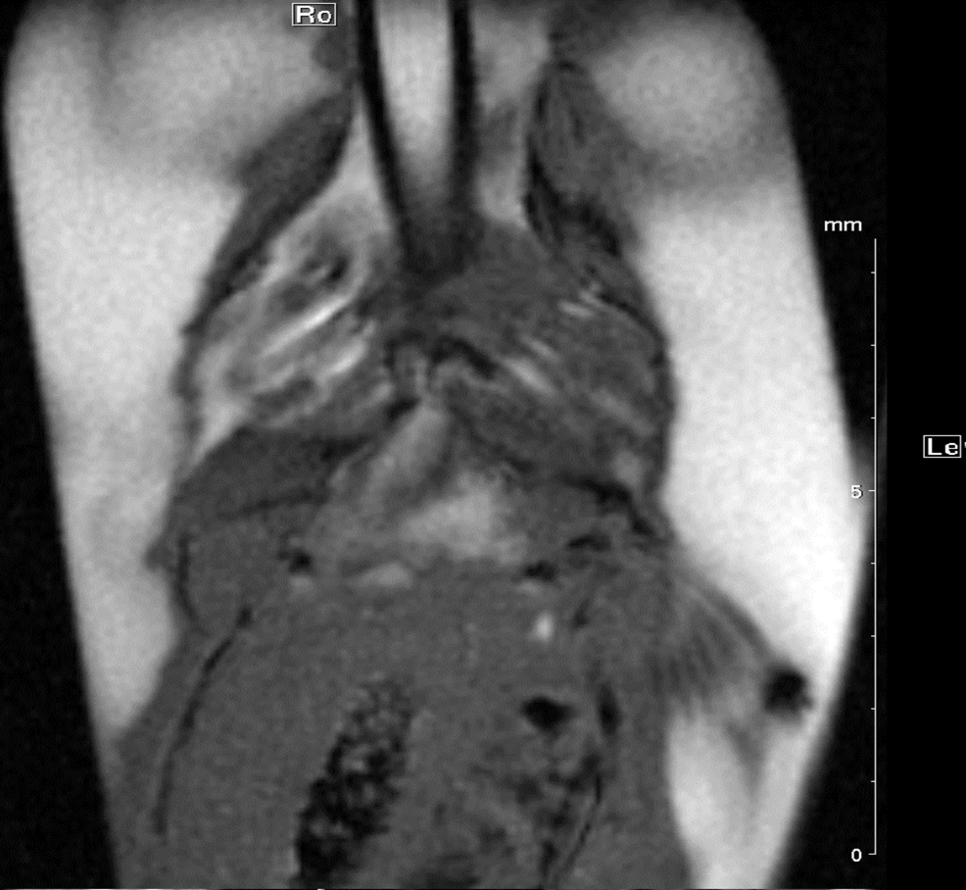

For our latest project, cine cardiac MR imaging of living adult zebrafish, the retrospective gating technique (IntragateTM Tool) is mandatory. The small size of the zebrafish heart, the ventricle comprises around 2 mm, and the fact that we deal with a fish makes, MRI quite challenging. Being able to use a cryogenically cooled 1H array coil, which gives us a much higher resolution and a better signal to noise ratio compared to a room temperature coil, we are able to image adult zebrafish hearts. The biggest challenge is the supply of the fish with oxygen during the measurements. We are using two cradle set-ups momentary: A chamber with water flow (Fig. 4a), which leads to a prolongation of measurement time, a more constant heart beat and less spontaneous movement of the anesthetized fish; but with this method the natural gill movement -which frequency is close to the frequency of the heart of the fish- is difficult to be separated from the heart movement.

Another possibility is to position the fish in a chamber without floating water so gill movement will stop, but due to the unfavourable situation with oxygen supply, only short measurement time is possible.